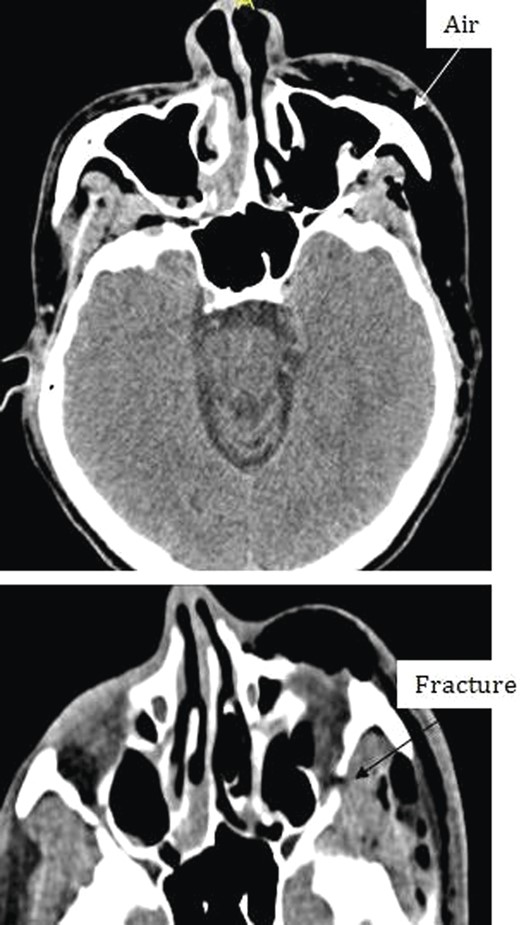

Chest X-ray and head, neck and chest computed tomography (CT) confirmed the diagnosis and extension of PM (Figs 1–3). CT revealed fracture of the floor of left orbit with soft tissue, fat herniation into left maxillary sinus roof, left orbital emphysema with no muscular entrapment. Gas was observed in periorbital tissues, left temporal scalp, infratemporal fossa, left parapharyngeal space and left cheek. Moreover, tissue planes in the neck revealed the presence of air particularly around the carotid vessels, in the posterior triangle and superior mediastinum (PM) around the thymus, trachea (middle), left side of the aorta and anterior to the sternum. However, on auscultation, lungs were clear with and the laryngeal passages and trachea looked normal.

Different levels of head imagining showing fracture of the floor of the orbit and subcutaneous air.